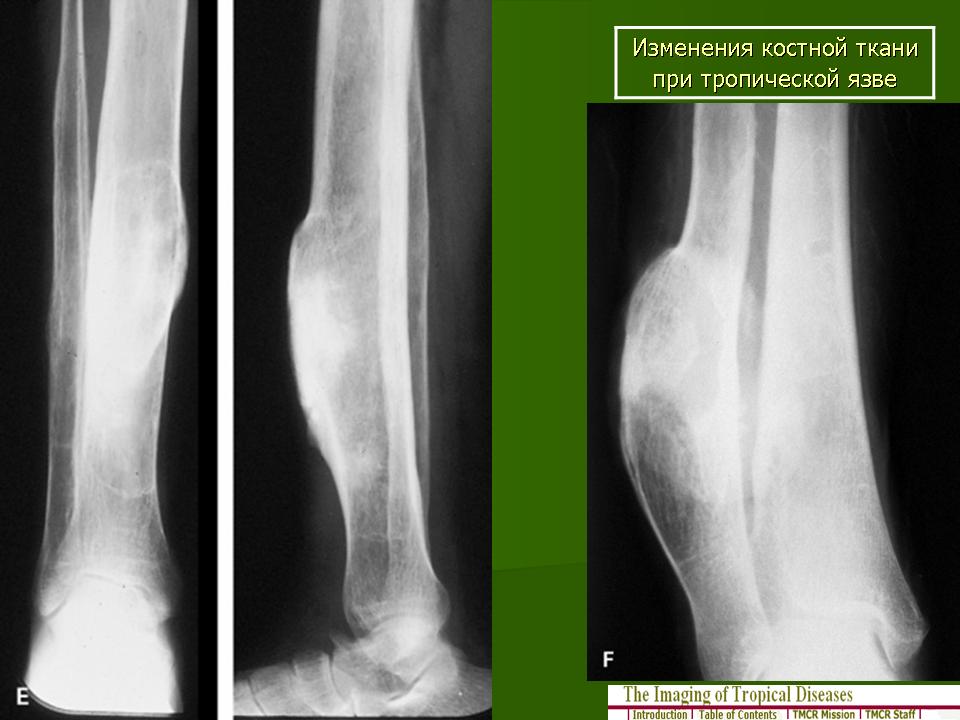

"Тропическая язва".